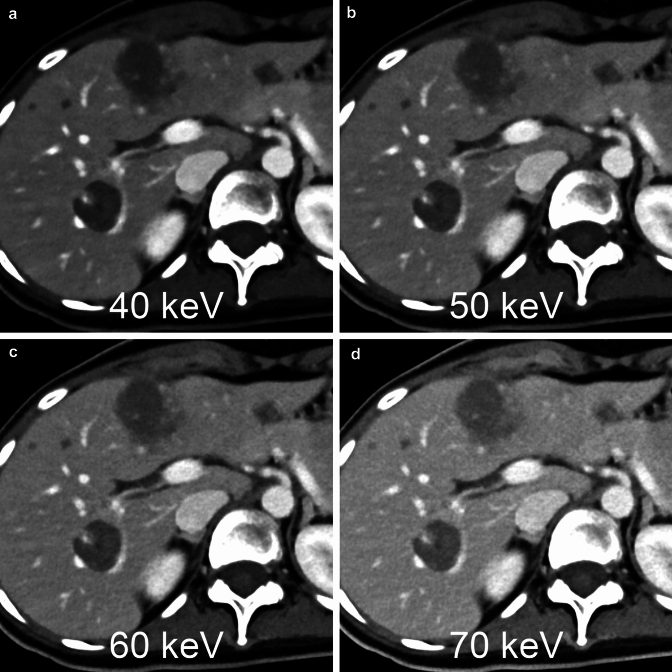

Fig. 4.

Using a photon counting detector, virtual monochromatic images of any energy level from 40 to 190 keV can be generated from 120kVp single-energy raw data. The lower the keV setting of the virtual monochromatic image, the higher the contrast between the liver lesion and the liver parenchyma

One of the major advantages of photon-counting CT in abdominal examinations is that it provides virtual monochromatic images with high image quality. The photon-counting detector is able to determine the energy intensity of the photons, making it possible to generate virtual monochromatic images from single-energy acquisition data at, for example, 120 kVp (Fig. 4). The minimum and maximum energy level settings for virtual monochromatic images in this CT system are 40 and 190 keV, respectively [24, 26]. The low-keV virtual monochromatic images with the photon-counting CT can provide superior performance over conventional single-energy (non-spectral) CT in arterial phase imaging, including significantly higher contrast-to-noise ratio, better image quality, and lesion conspicuity [27]. The low-keV virtual monochromatic images with the photon-counting CT have a significantly higher contrast-to-noise ratio with similar subjective image quality as compared to conventional single-energy dual-source CT at identical radiation dose [24].

The mainstream of conventional dual-energy CT is to scan with two different energy X-ray beams, for example 80 kVp and 140 kVp, and analyze the data to generate virtual monochromatic images [28]. Therefore, prior to scanning, a decision had to be made whether to perform dual-energy imaging or normal single-energy imaging. The design of the photon-counting detector allows virtual monochromatic images to be reconstructed from single-energy data acquired at 120 kVp or 140 kVp. There is no need to decide on the type of acquisition before scanning, considering whether the virtual monochromatic imaging is needed or not [19]. For the virtual monochromatic images at energies below 60 keV, the contrast-to-noise ratio of the photon-counting CT images was generally higher than that of the corresponding energy-integrating detectors dual-energy CT images [29].

Scanning protocols optimized for the abdominal diseases

Virtual monochromatic images are available with acquisition at 120 kVp or 140 kVp of X-ray tube voltage. Because acquisition at 140 kVp provides the best possible spectral separation at the detector level [31], Schwartz et al. acquire all adult abdominal CT images at 140 kVp [19]. When performing abdominal photon-counting CT, many radiologists are concerned with determining which keV setting of virtual monochromatic image reconstruction is optimal for diagnosis. The 40 keV images have the best contrast-to-noise ratio for abdominal organs, vascular structures, and hypovascular liver metastases [24, 26]. However, CT image quality may be affected by factors other than the contrast-to-noise ratio. Racine et al. reported that the highest detectability was found at 65 and 70 keV for both hypoattenuating and hyperattenuating objects, regardless of phantom size and radiation dose, in the phantom study, which was performed assuming the detection of hepatocellular carcinoma [32]. Higashigaito et al. reported that the overall image quality of abdominal CT tended to be higher at 50 keV and 60 keV compared with energy-integrating detector CT, whereas the overall image quality was lower at 40 keV compared with energy-integrating detector CT in the clinical study [24]. Further studies may be needed to determine the optimal keV setting for diagnostic abdominal CT using photon-counting CT in clinical practice.